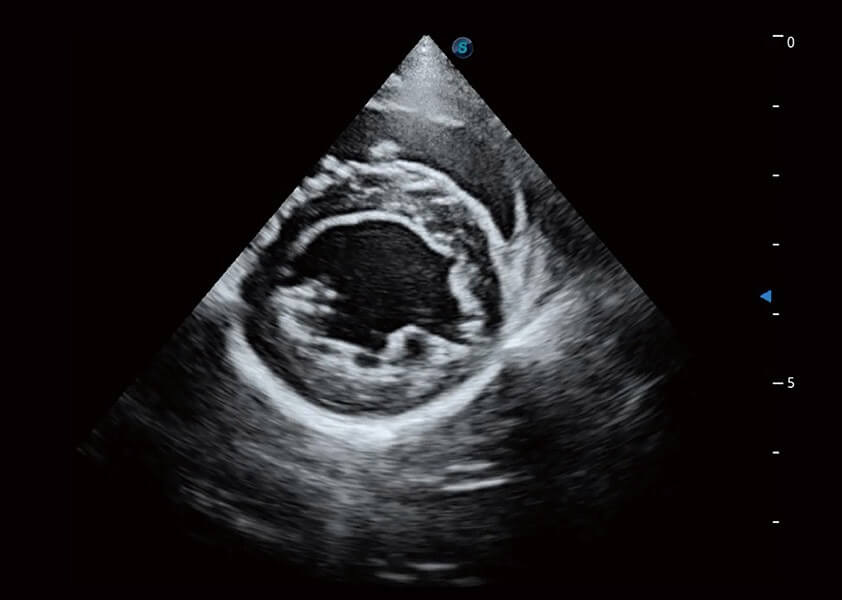

ProPet 60 作为一款高端台式动物超声设备,为动物医生的日常诊断提供了一系列贴合动物临床需求、解决临床实际问题的高级成像功能。凭借全系列高清探头,满足医生对腹部、心脏、生殖、浅表、肌骨等成像的所有需求,切实帮助您提升检查效率,提高诊断信心。

动物是人类最亲密的朋友和最值得信赖的伙伴。玖鼎集团也一直致力于探索动物专用的超声影像解决方案。 全新推出的ProPet系列,是玖鼎集团在动物超声影像智能化、专业化、精准化的一次跨越式革新。动物不能用言语来表述自己的不适,通过超声影像,ProPet系列搭建了动物医生与不同物种沟通的“桥梁”,为动物医生注入了“治愈之力”。